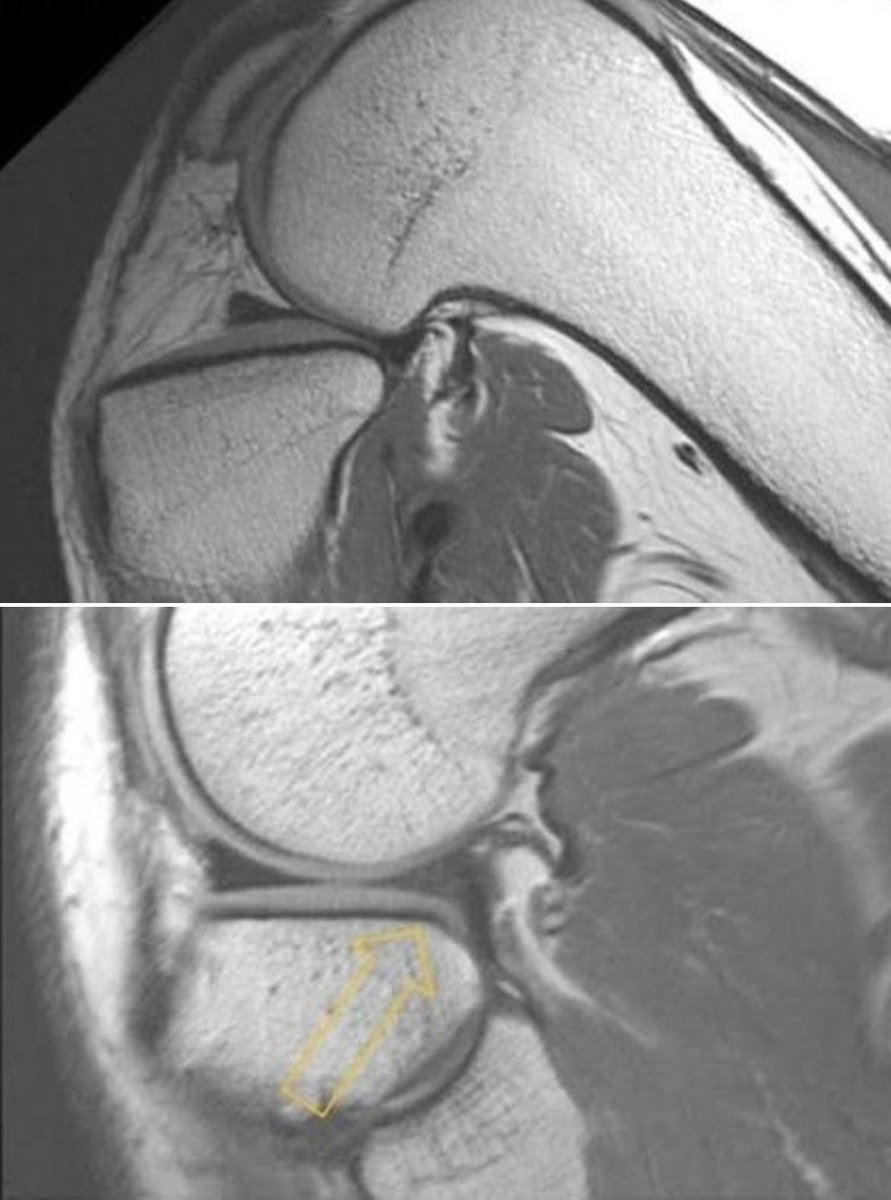

Interesting phenomenon: I call this the "pre" root tear with increased tibial signal but intact meniscus root.

When I see a patient that fits the demographics of a meniscus root tear with large knee effusion and posteromedial pain, I am more aggressive with MRI's. Have been seeing more of these as a result.

Have had good success in treating these with restricted weightbearing alone. (with permission)